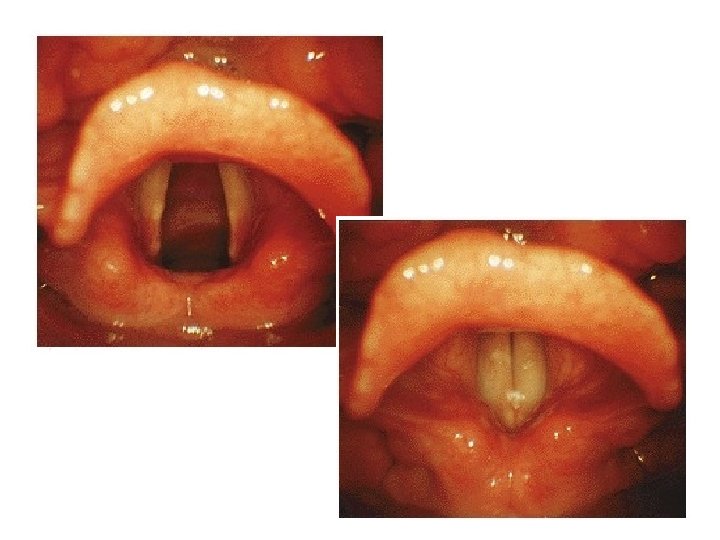

Hrtan pohyby Hlasivky Rotace – vnitřní x vnější Abdukce x Addukce Zkrácení x Prodloužení Aditus laryngis Zúžení x Rozšíření lig. vocale x lig. vestibulare m. vocalis epitel mnohovrstevný dlaždicový na hlasivkách, jinde víceřadý cylindrický s řasinkami

Hrtan - Cavitas laryngis • Vchod = Aditus – epiglottis, incisura interarytenoidea, plica aryepiglottica (tuberculum corniculatum + cuneiforme) • Předsíň = Vestibulum (nesprávně Supraglottis) – plica vestibularis – ligg. vestibularia nepravé vazy, – rima vestibuli, ventriculus, (sacculus) • Hlasivka = Glottis – plica vocalis – ligg. vocalia, rima glottidis pravé hlasivkové vazy • Podhlasivková dutina = Cavitas infraglottica